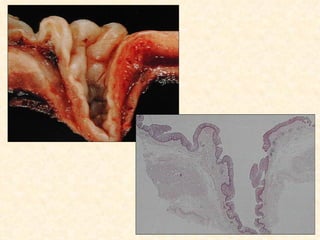

Esofagite cáustica

 Ácidos

 Álcalis

 Outras substâncias corrosivas

 Evolução

    Necrose e dissolução

    Inflamação

    Estenose

 (radioterapia)

Esofagite cáustica  Ácidos Álcalis  Outras substâncias corrosivas  Evolução  Necrose e dissolução  Inflamação  Estenose  (radioterapia)